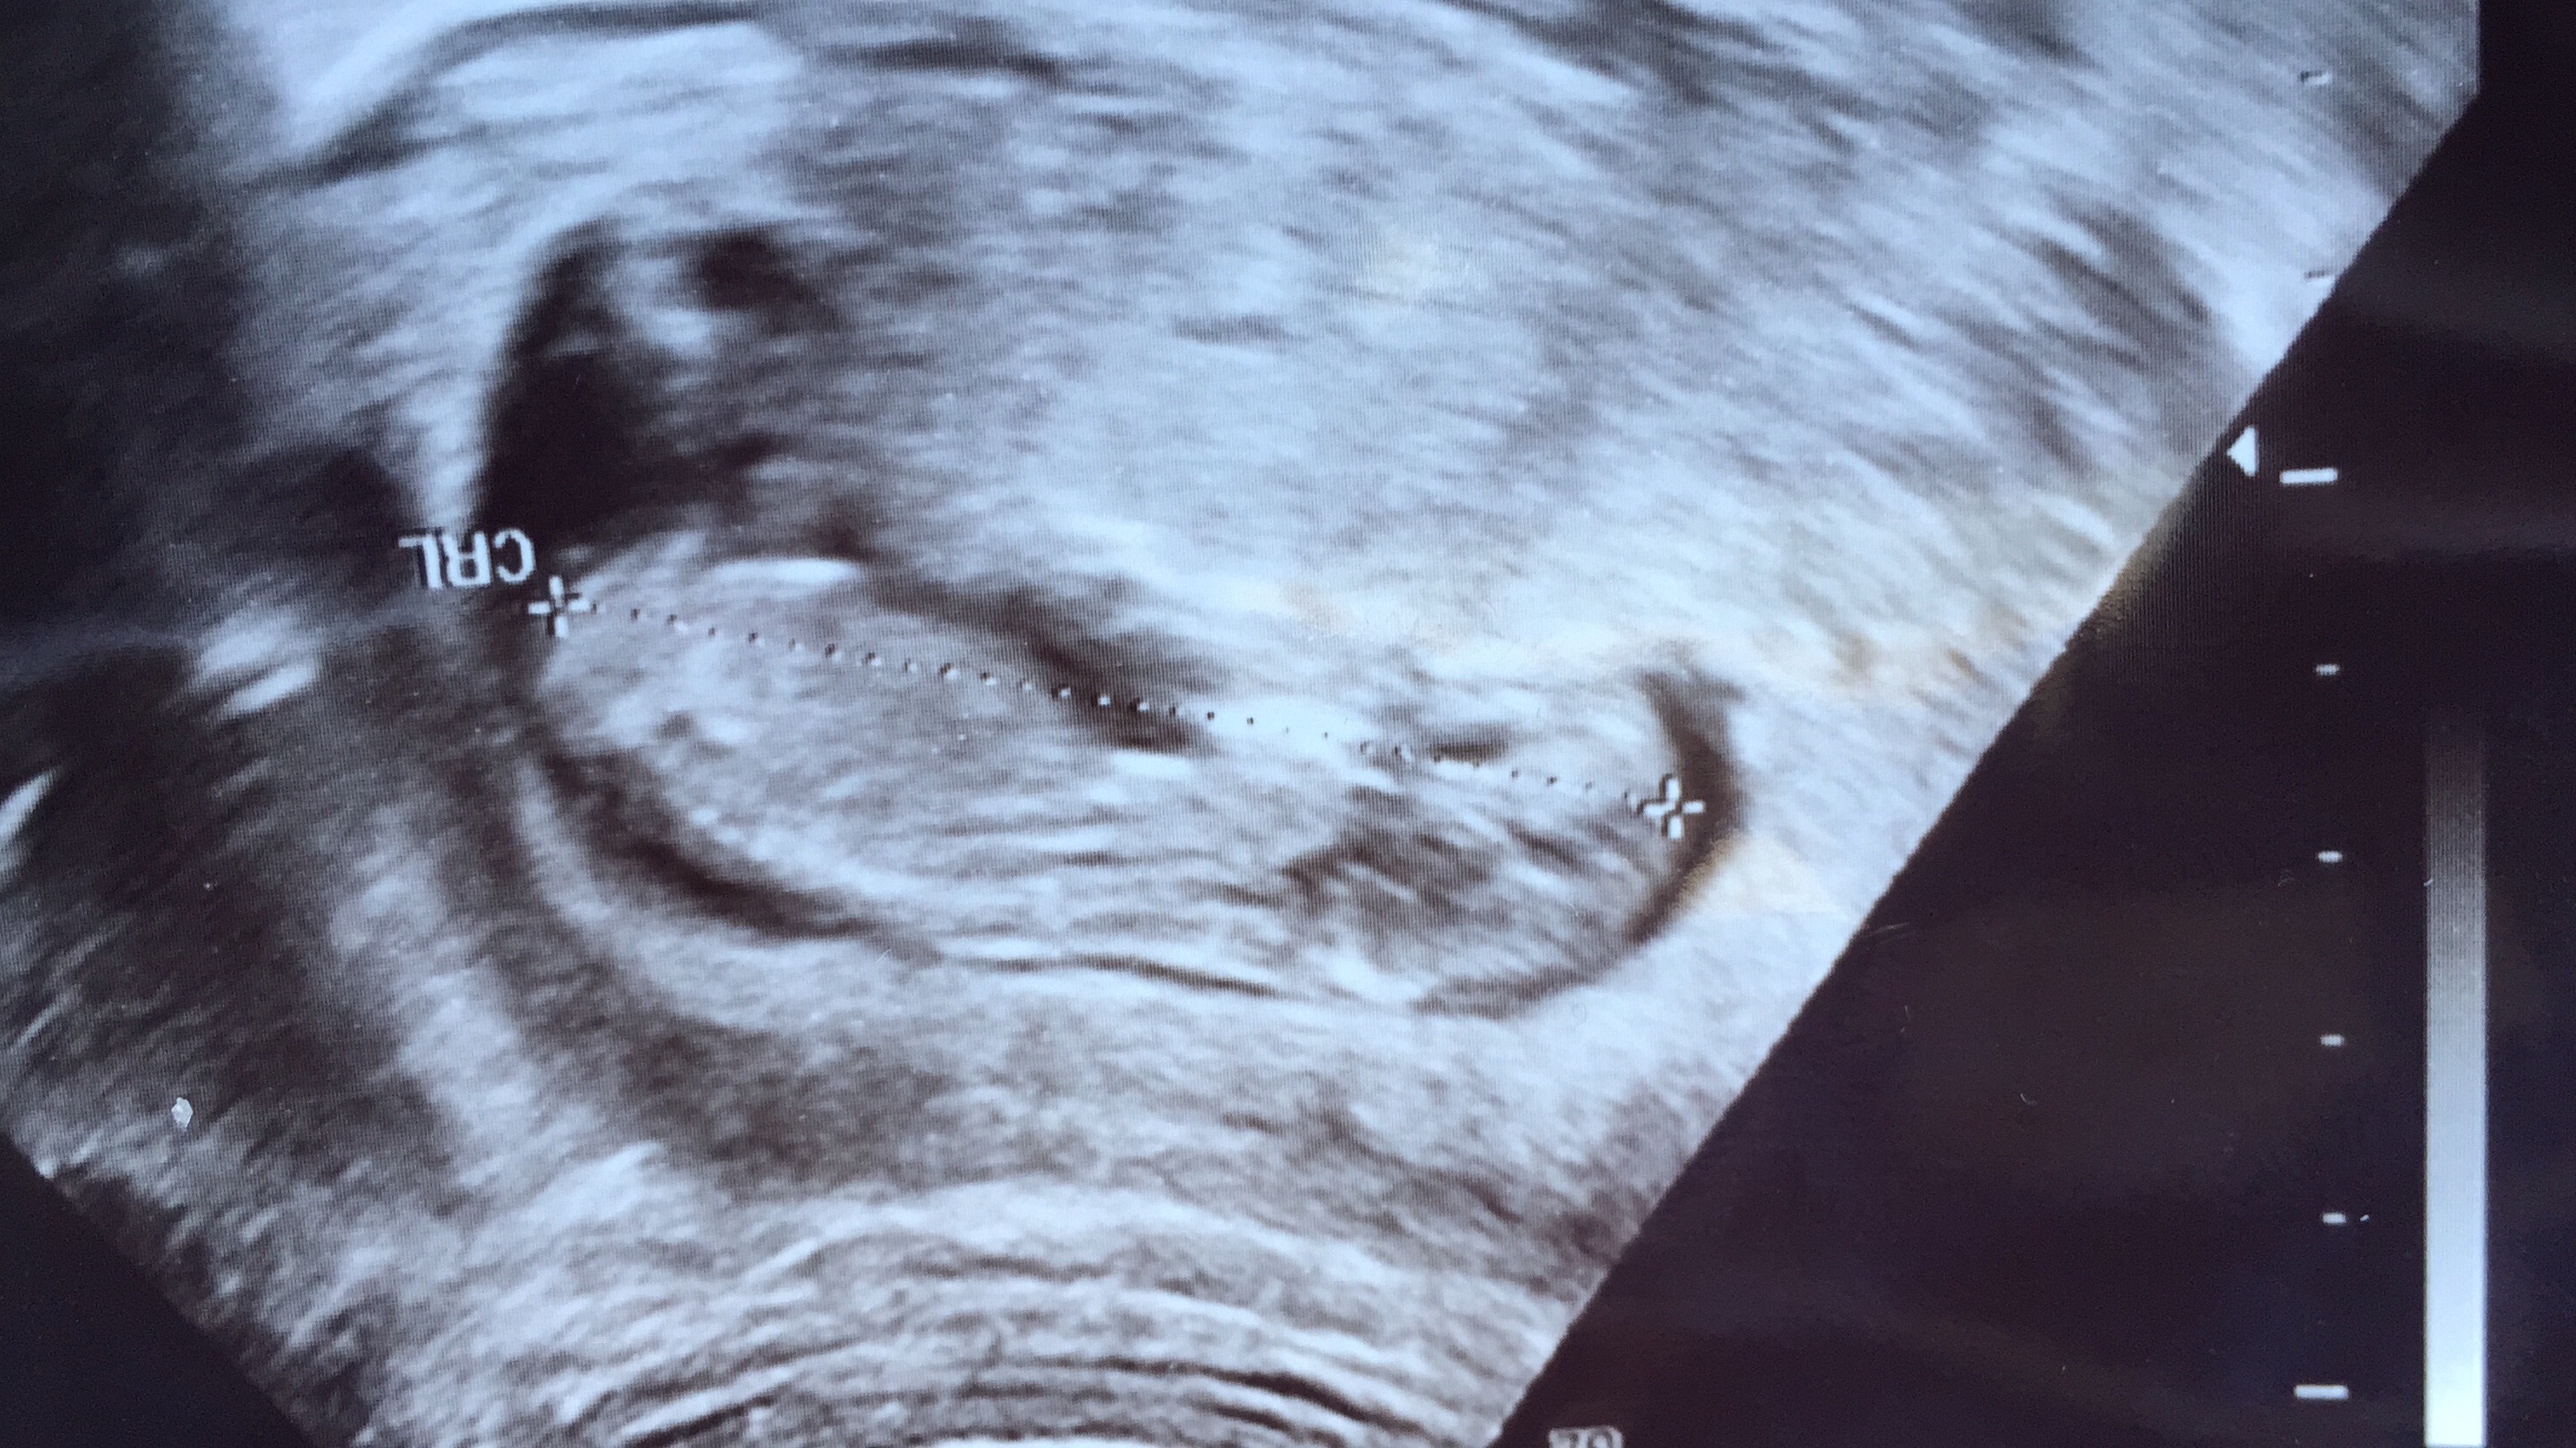

Merhaba 12+4 ve 13+0 lık ultrason görüntülerimiz. Kahve çekirdeği gibi bir çıkıntı var ancak kız ya da erkek diye yorum yapamıyorum sesi. Sizin fikriniz nedir?